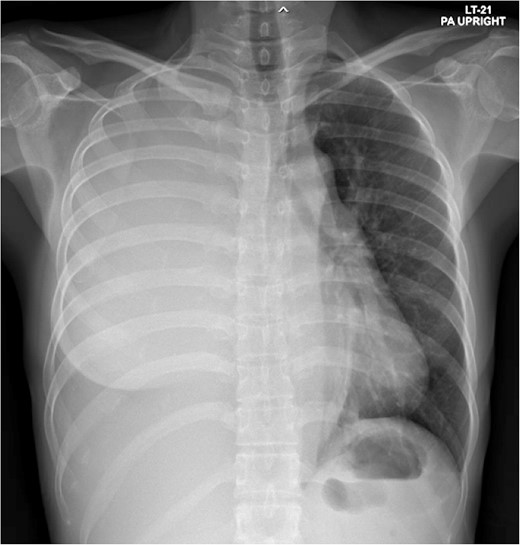

A 33-year-old Asian female presented with progressive dyspnea for 1 month. Physical examination revealed decreased breath sounds at right lung with dullness on percussion and abdominal distension. A chest X-ray showed a large right-sided haziness (Fig. 1). Blood test revealed hemoglobin 11.9 g/dl, WBC 13 200 cells/mm3, protein 8.3 g/dl, albumin 3.5 g/dl, total bilirubin 0.5 mg/dl, direct bilirubin 0.13 mg/dl, and alkaline phosphatase 67 U/l. Computed tomography (CT) scan demonstrated a large amount of ascites and right pleural effusion, 1.5-cm peritoneal nodule at the right subdiaphragmatic surface (Fig. 2), multiple ovarian cysts, and 2.6-cm hypodense lesion at posterior wall of cervix abutting upper rectum.

Total opacity of right hemithorax caused mediastinum shifting to the left. This finding was consistent with massive right pleural effusion.